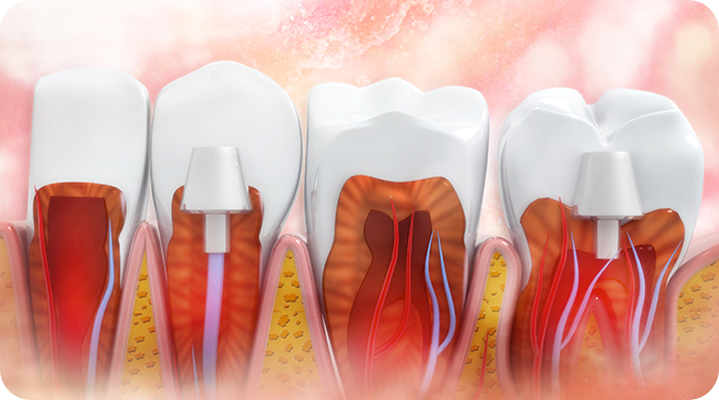

“자연치아 살리기 최우선 진료”

서울하나치과는 자연치아의 가치를 알기에 언제나 자연치아를 우선적으로 보존하기 위해 노력합니다.

건강한 치아는 건강한 잇몸이 있기에 존재합니다. 성인 대부분이 잇몸 질환을 모르고 방치하고 있습니다. 잇몸질환, 더 이상 방치하지 말고 관리를 통해 개선해보세요!

PERIODONTAL DISEASE

치주낭 길이 3mm 이하

치주낭 길이 3~5mm 이하

치주낭 길이 5~7mm 이하

치주낭 길이 7mm 이상